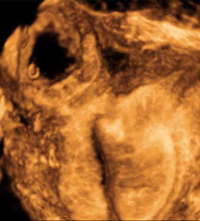

UCSF’s ultrasound specialists are experts in fetal development and perform approximately 3,500 fetal ultrasound studies per year. The ultrasound subspecialty has been instrumental in developing and supporting a growing Fetal Treatment Center at UCSF. We perform all of the high-risk obstetrical sonograms of patients referred to UCSF for potential fetal therapy, and in this role we consult and collaborate with the perinatologists, geneticists and pediatric/fetal surgeons.

Cardiac teratoma and pericardial effusion.

Our physicians are experts in the diagnosis of fetal anomalies including: